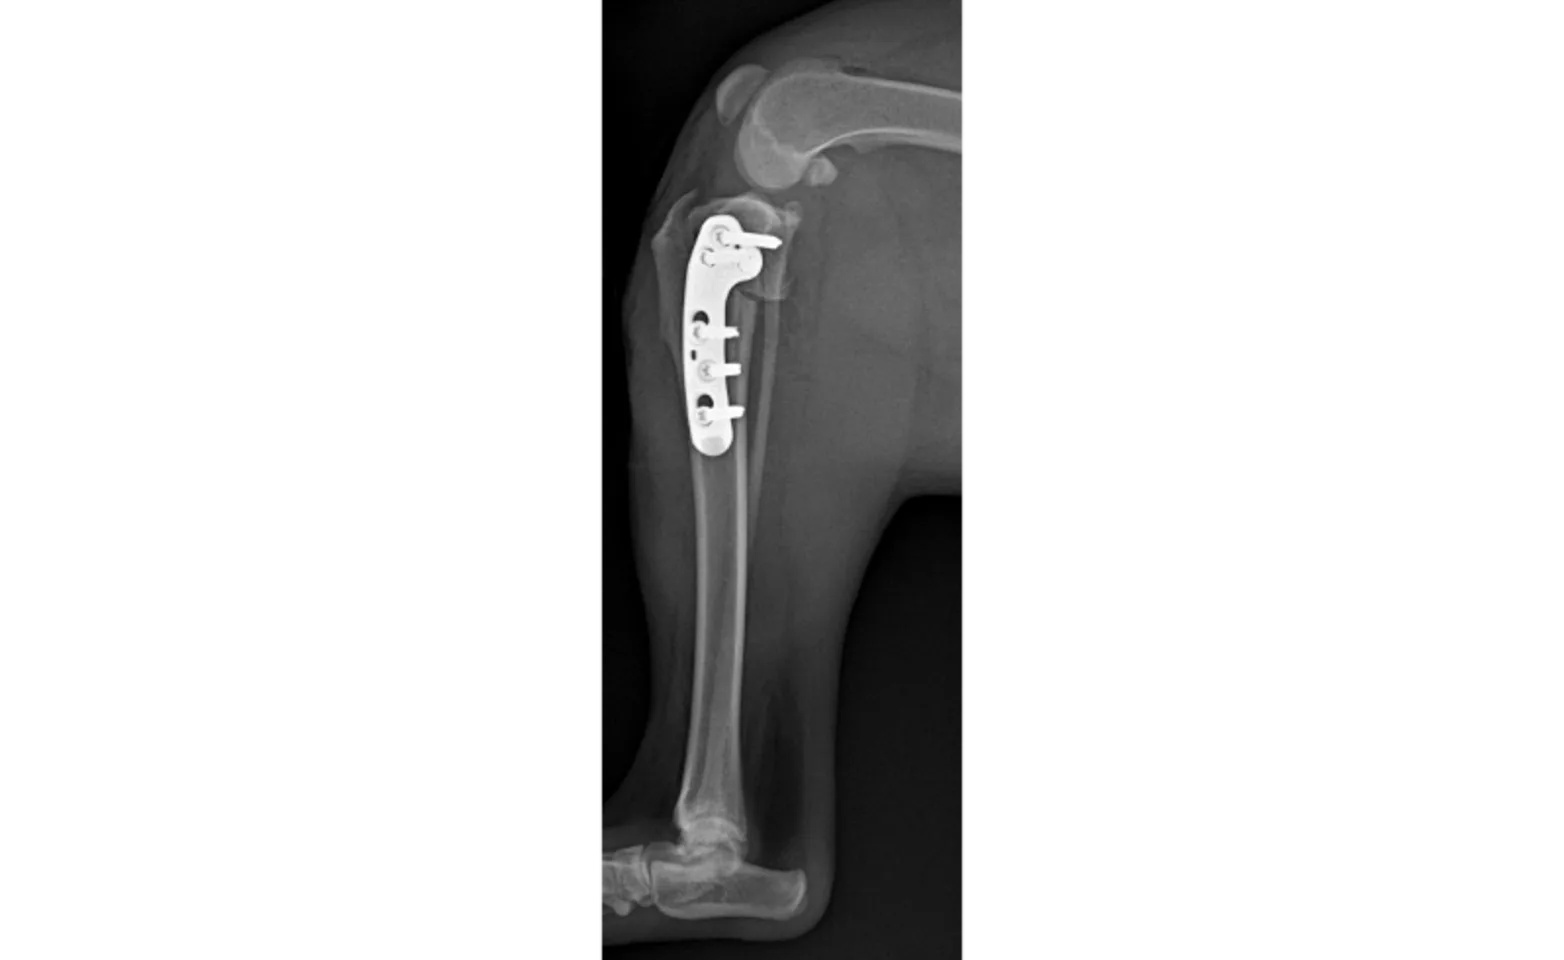

Next, a semicircular cut is made into the top portion of the tibia and the segment is rotated backward to create a flatter tibial slope. The two pieces of bone are then held in place with a stainless steel bone plate that is screwed onto the bone. See the X-rays pre and post-TPLO surgery (fig 2 [Pre-op. Steep slope.] & fig 3 [Post-op. Flatter slope]).

Follow-up – All TPLO patients are recommended to have an 8-10 week post-op X-ray to assess bone healing. Recommendations for returning to normal activity will be given after assessment of the X-rays.